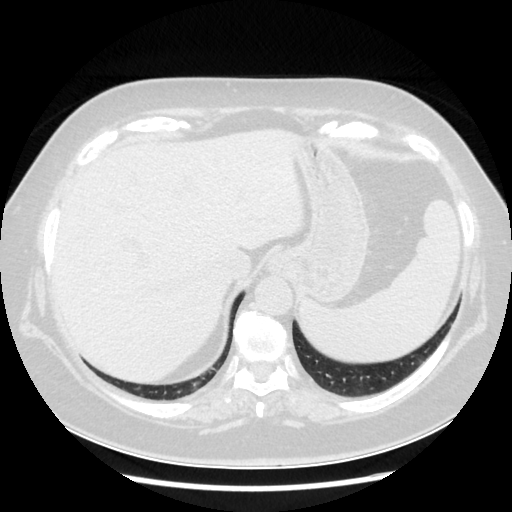

Original NATIVE CT scan (input)

Full window (WL 1023.5, WW 4095 β†’ Low βˆ’1024, High +3071)

Lung window (WL -600, WW 1500 β†’ Low βˆ’1350, High +150)

Mediastinum window (WL 40, WW 400 β†’ Low βˆ’160, High +240)